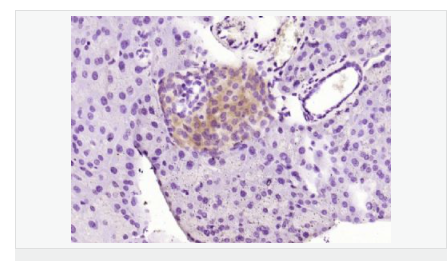

| 產品應用 | WB=1:500-2000 ELISA=1:5000-10000 IHC-P=1:100-500 IHC-F=1:100-500 IF=1:100-500 (石蠟切片需做抗原修復) not yet tested in other applications. optimal dilutions/concentrations should be determined by the end user. |